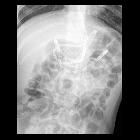

Infant after

feeding tube placement. AXR AP shows the tip of the nasogastric tube is in the stomach. The tip of the feeding tube is seen to cross the midline through the pylorus, descend through the duodenum, and then course through the proximal jejunum.The diagnosis was correct position of the feeding tube.